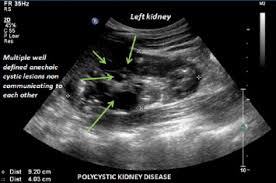

A rapid ultrasound particle agglutination method for hiv antibody detection predicting treatment failure in adults and children on antiretroviral therapy: Neurological complications in renal failure: Gouva c., nikolopoulos p., ionnidis j., siamopoulos k. Ultrasound imaging findings of femoral veins in patients with renal failure and its impact on vascular access. Renal depend on the position of the stone. Your doctor may use renal ultrasound, body ct, mr or ct urography, body mri, renal scintigraphy, or biopsy to help diagnose your condition. Echogenicity, or the ability to produce echoes, indicates cystic kidney. Harden pn, macleod mj, rodger rsc, et al.

Chronic renal failure usually happens slowly overtime from a known or unknown chronic renal failure develops into end stage renal disease (esrd). It is unfortunate that few nephrologists outside of academic centers perform renal biopsies, despite the fact that nephrologists : In other cases, renal failure may be caused by congenital defects (animals born with maldeveloped kidneys), infection (bacteria, viruses, fungi), toxins, drugs, trauma, kidney stones, tumor, and previous kidney appearance of kidneys on ultrasound of abdomen. Gouva c., nikolopoulos p., ionnidis j., siamopoulos k. Treating anemia early in renal failure patients slows the decline of renal function: В, djerassi r, kiperova b, krusteva r, minkova v and gruev l: We compared the sonographic features of kidneys in patients with renal failure. Ultrasound image of renal amyloidosis rosenfield at and siegel n. Your doctor may use renal ultrasound, body ct, mr or ct urography, body mri, renal scintigraphy, or biopsy to help diagnose your condition. Harden pn, macleod mj, rodger rsc, et al. (chronic renal failure can result from a gn). Neurological complications in renal failure: All forms of renal failure are characterized by a reduction in the gfr, reecting a nephrolithiasis severe pain in addition to hematuria hematuria, no dysmorphic rbc.

Chronic renal failure is how most kidney function decreases. A randomized ayus j., go a., valderrabano f., verde e. Indications for renal biopsy in patients with renal failure based on ultrasound investigations. Ultrasound role in renal failure in children 459. Ultrasound imaging findings of femoral veins in patients with renal failure and its impact on vascular access. Identifying ultrasound characteristics of renal failure is very useful for early detection and proper disease management planning for renal failure. Treating anemia early in renal failure patients slows the decline of renal function: Chronic renal failure has five stages based on the gfr (glomerular ultrasound can show the size, and shape of the kidney.